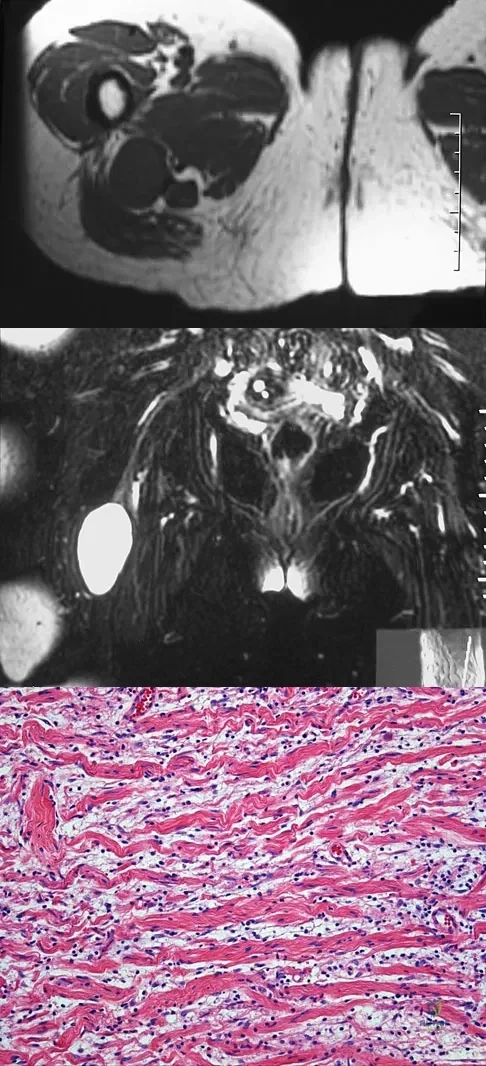

A 37-year-old man pulled his hamstring playing softball 3 weeks ago. The patient had not noted any mass prior to his injury. MRI scans of the posterior thigh are shown in Figures 4a and 4b. Figure 4c shows the biopsy specimen from a needle biopsy. What is the most likely diagnosis?

Explanation